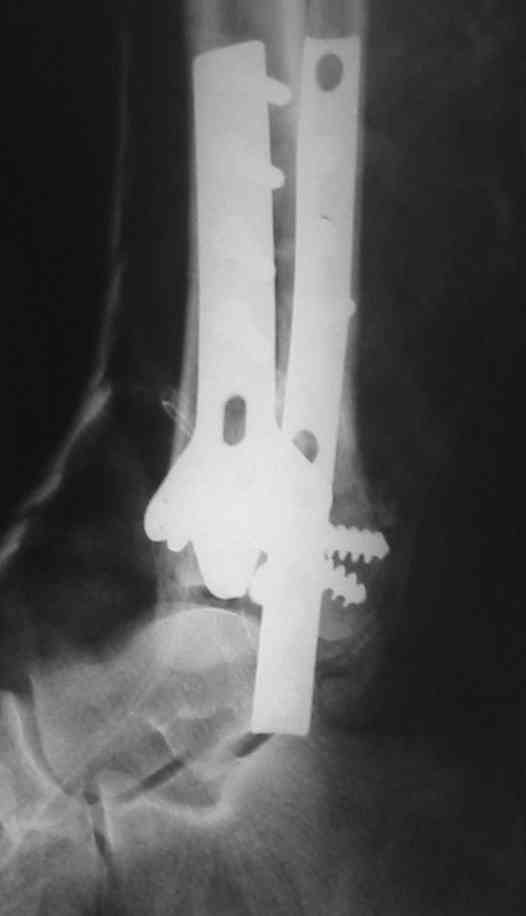

OK, Dr Driagin,

Ja operiroval bolnogo po Vashemu, hotia sam ni ochen' ubezden' v itom, t.k. bolnoi otkazalsa na proch' ot ex.fix, ja emu sdelal ORIF + Kostnia plastika, snimky prelogiottsa,

segodnia na pereviazky koza naprezena, preshlos' sdelat' nadsechky, kak bi ee nicroz ni nachilsa, vot pochemu ni lublu otkrito vmeshatsa zdes',